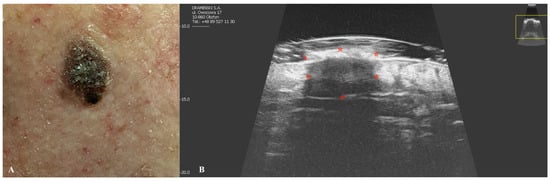

2. Basal Cell Carcinoma

| Basal Cell Carcinoma | Oval, hypoechogenic lesion with well-defined borders. Hyperechoic spots (“cotton flower” pattern) may be present. Poor vascularization on Doppler. |